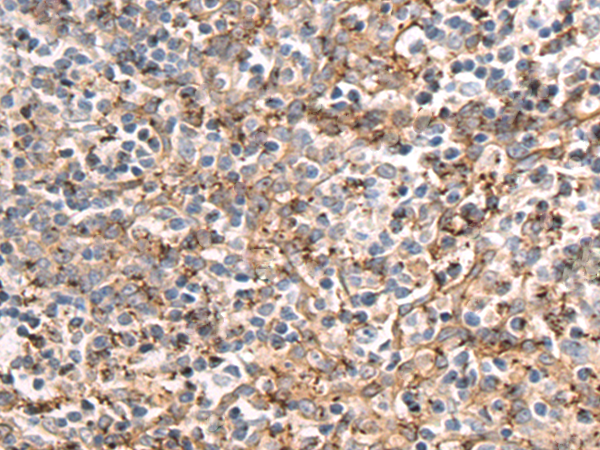

分类: 科研抗体货号: P10641别名: ACEH应用: IHC反应种属: Human, Mouse, Rat